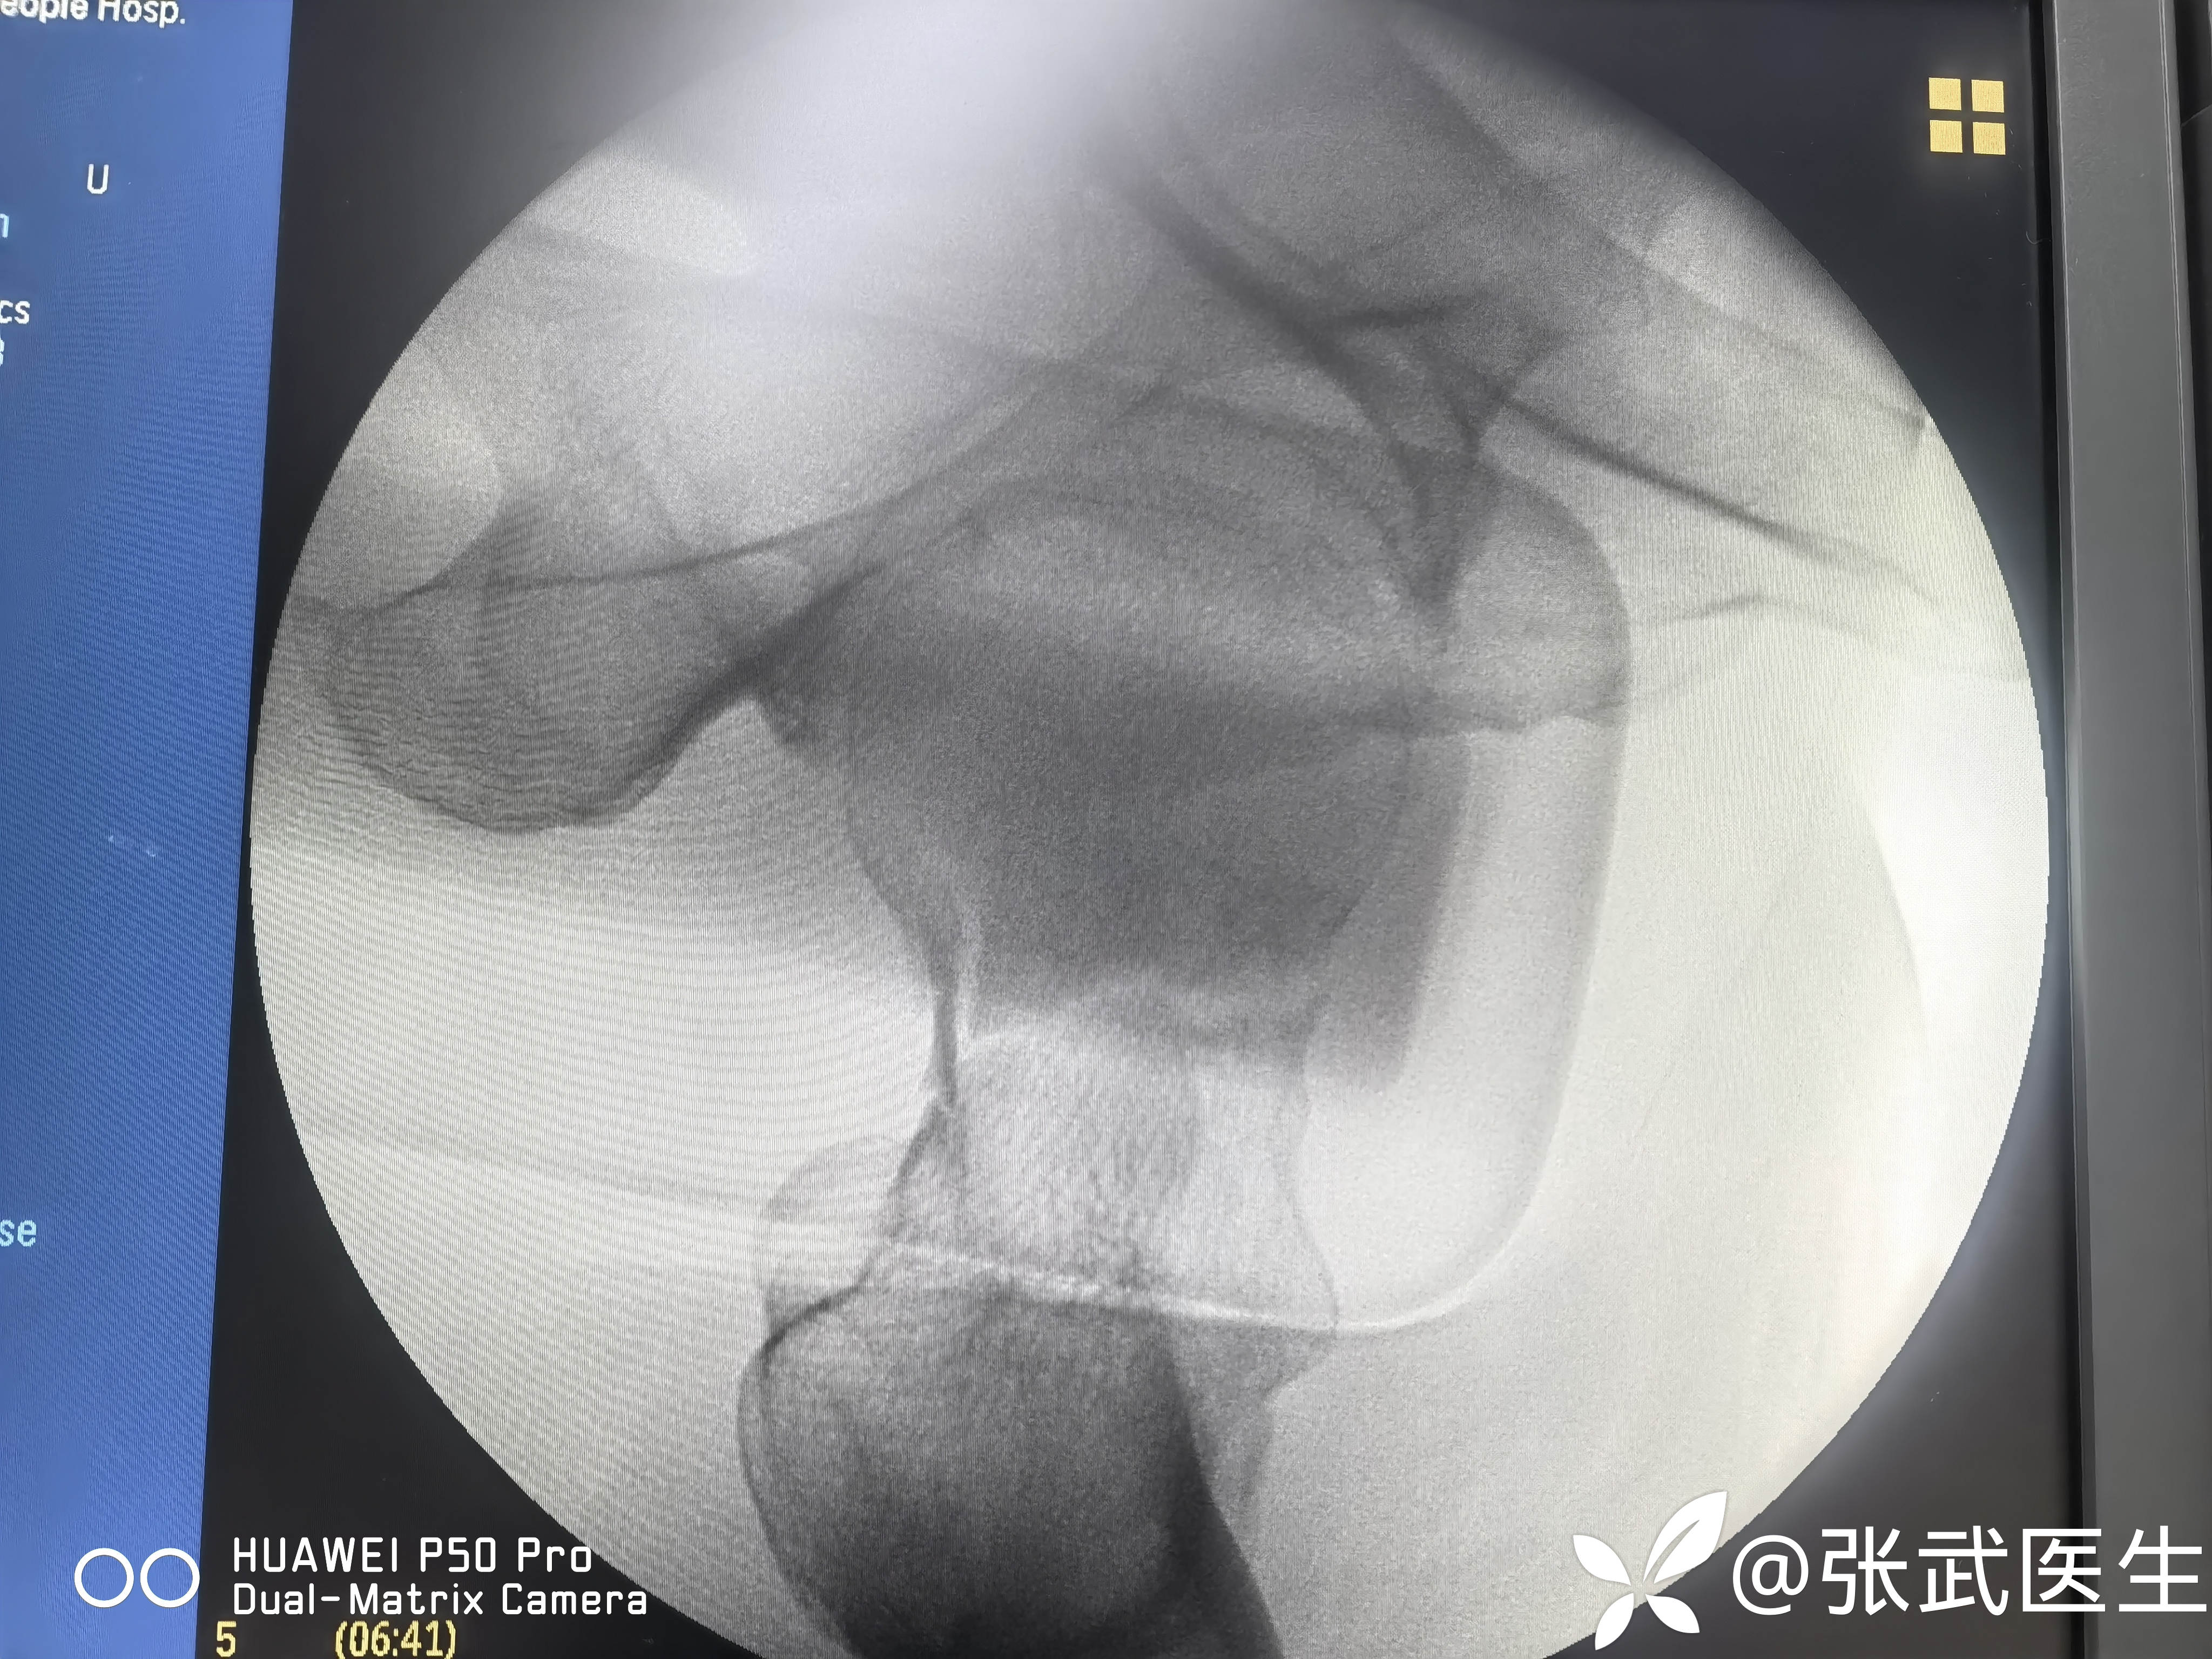

骨折复位情况

骨折复位